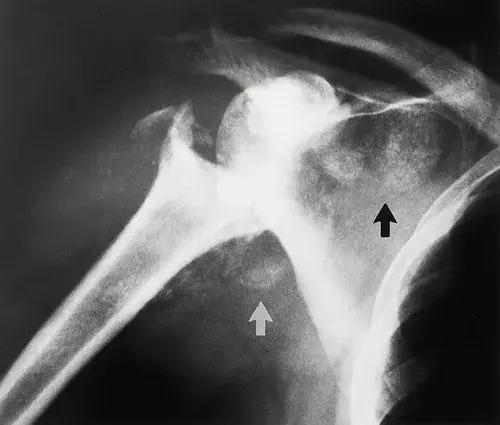

图1:45岁男性,肩关节神经性骨关节。 (a)X线片显示类似于截肢的骨溶解,具有明确的边缘。 在剩余的肱骨中维持正常的矿化。 碎屑排列在扩张的关节囊,肩胛下凹陷(黑色箭头)和腋窝凹陷(白色箭头)。 (b)颈椎的T1加权自旋回波MR图像(重复时间毫秒/回波时间msec = 500/20)有助于确认是否存在空洞(箭头)。 (来自美国放射学院[ACR]学习档案,MSK案例235.)